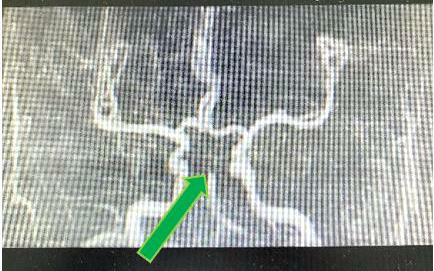

颅脑MRA示双侧大脑后动脉及双侧小脑上动脉未见显影,基底动脉远端闭塞